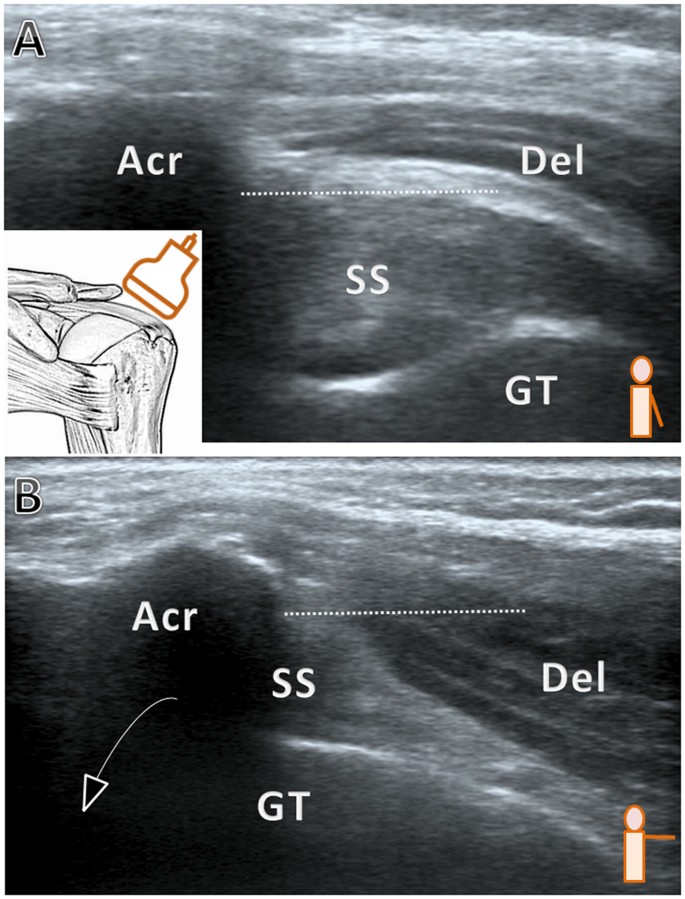

*Frontiers | Reliability of point-of-care shoulder ultrasound *